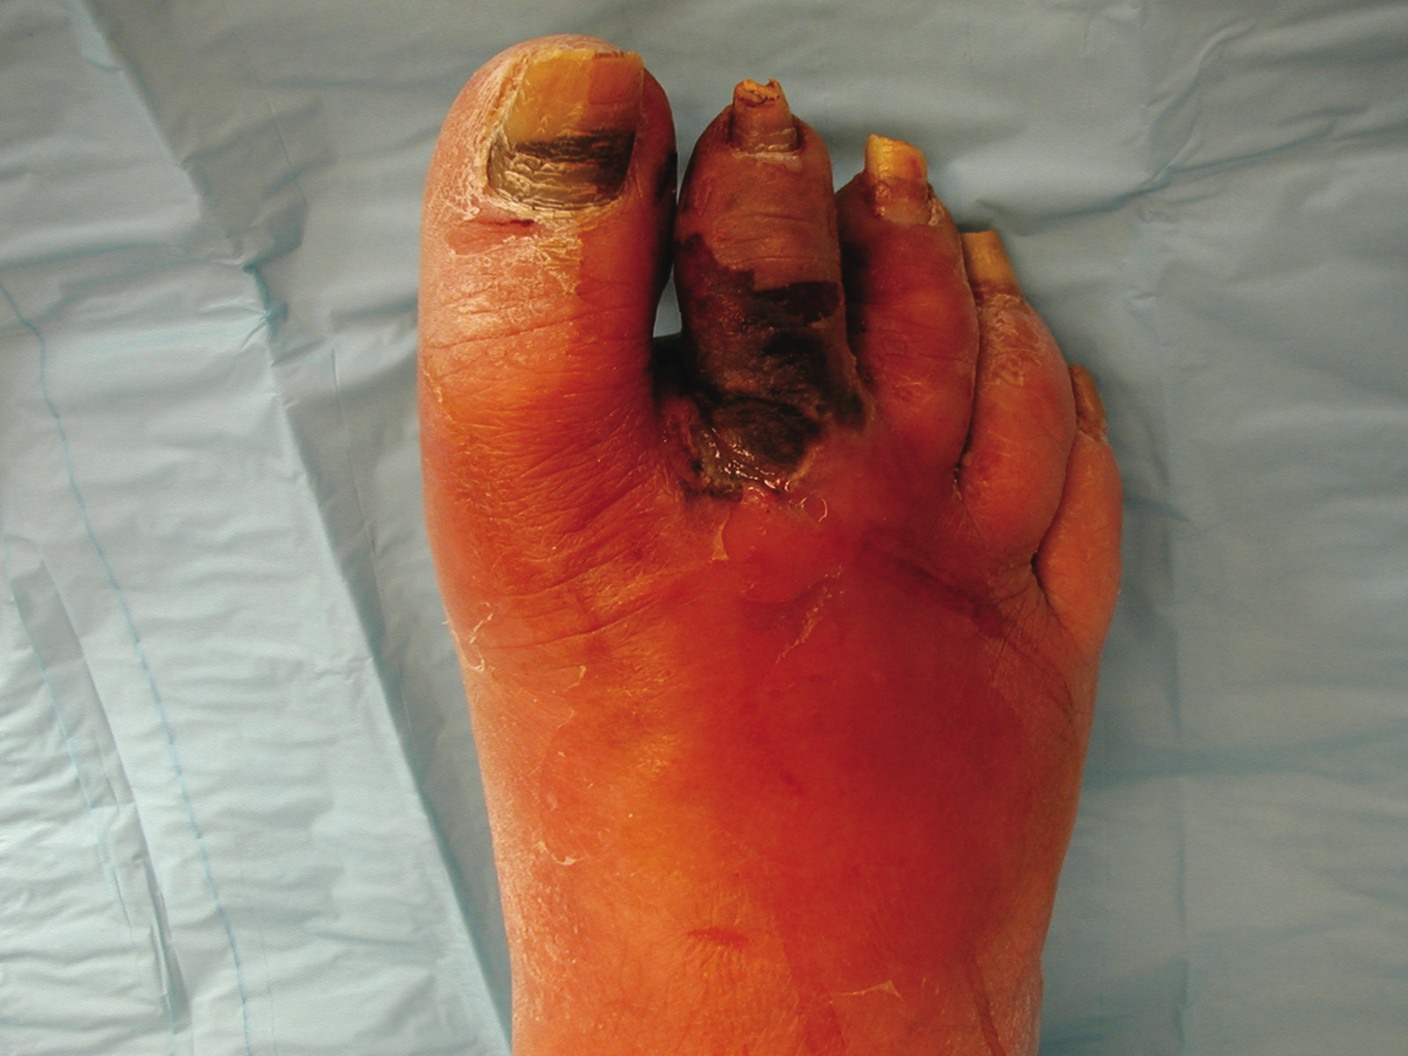

Study Examines Test For Diabetic Ulcer Risk

By Brian McCurdy, Senior Editor While there are a variety of screening methods to help identify those at risk for diabetic complications, a new modality may aid physicians in detecting systemic microcirculatory changes that signal a greater risk of diabetic complications. In a recent abstract presentation at the American Heart Association conference, researchers assessed the potential impact of hyperspectral technology cutaneous oxygenation monitoring (HTcOM). Using interim data from an ongoing study by the National Institutes of Health (NIH) and the National Institute of Diabetes and Digestive and Kidney Diseases (NIDDK), the study authors evaluated 162 diabetic patients with HTcOM. In using this technology, researchers found that patients with diabetic foot ulcers had lower oxyhemoglobin (HT-Oxy) in their forearms and palms than those without ulcers, according to the abstract. “(Patients) with poorer systemic microcirculation as manifested by lower HTcOM readings on the forearm were significantly more likely to have or develop a foot ulcer than other (patients) considered at high risk by standard clinical assessment,” point out the authors in the abstract. Abstract co-author Aristidis Veves, MD, DSc, cites the HTcOM’s simplicity, noting it is not time consuming and there is minimal training necessary to analyze the images. HTcOM can potentially identify patients at risk of ulceration and at risk of failing to heal their ulcer, says Dr. Veves, an Associate Professor at Harvard Medical School. He notes that more research regarding the test’s sensitivity and specificity will be required.